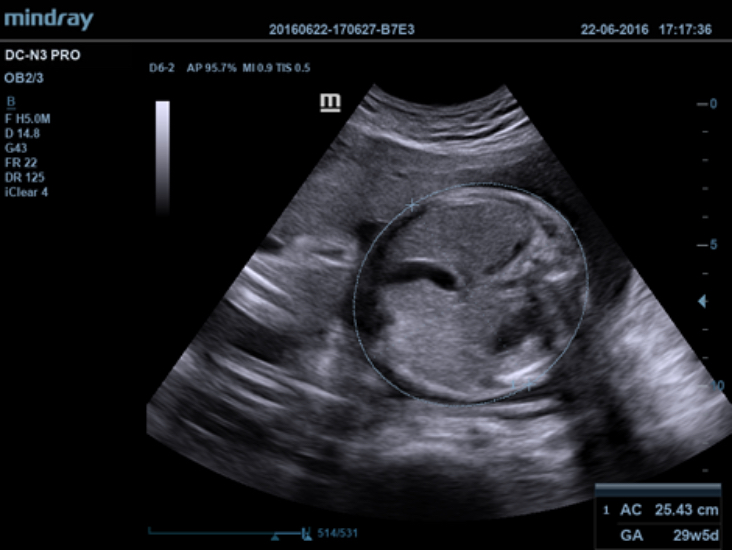

DC-N3 PRO

DC-N3 PRO? ??? ??? ??, ???, ???? ?? ???? ??? ?? ?????. ?? ??? DC-N3 PRO? ??? ??? ?? ??? ??? ???? ???? ??? ????? ??????. ???? ?? ???? ???? ?? ??? ???? ???? ???? ?? ? ????.

DC-N3 PRO? ??? ??? ?? ??? ??? ????? ?? ???? ???? ??? ?? ??? ??? ?? ???? ??? ?????. ?? ??? ??, ???, ??? ?? ??? ??? ??? ?????. ????? ???? ???? ????? ??? ???? ??? ?? ?? ?? ??? ??? ???? ??? ?????.

??? ??? ?? ?? ?? 4?? ??? ????? ??? ?? ???? ?? ??? ??? ??? ? ????.